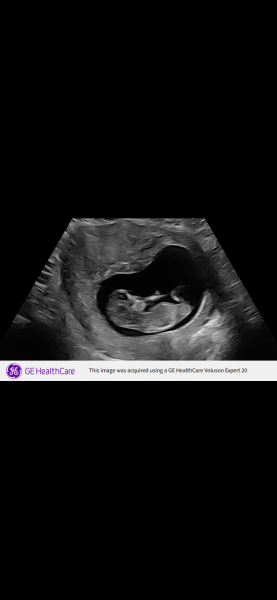

Hhhhmmm · 06/12/2025 13:40

Can you tell

Is it a boy or a girl?